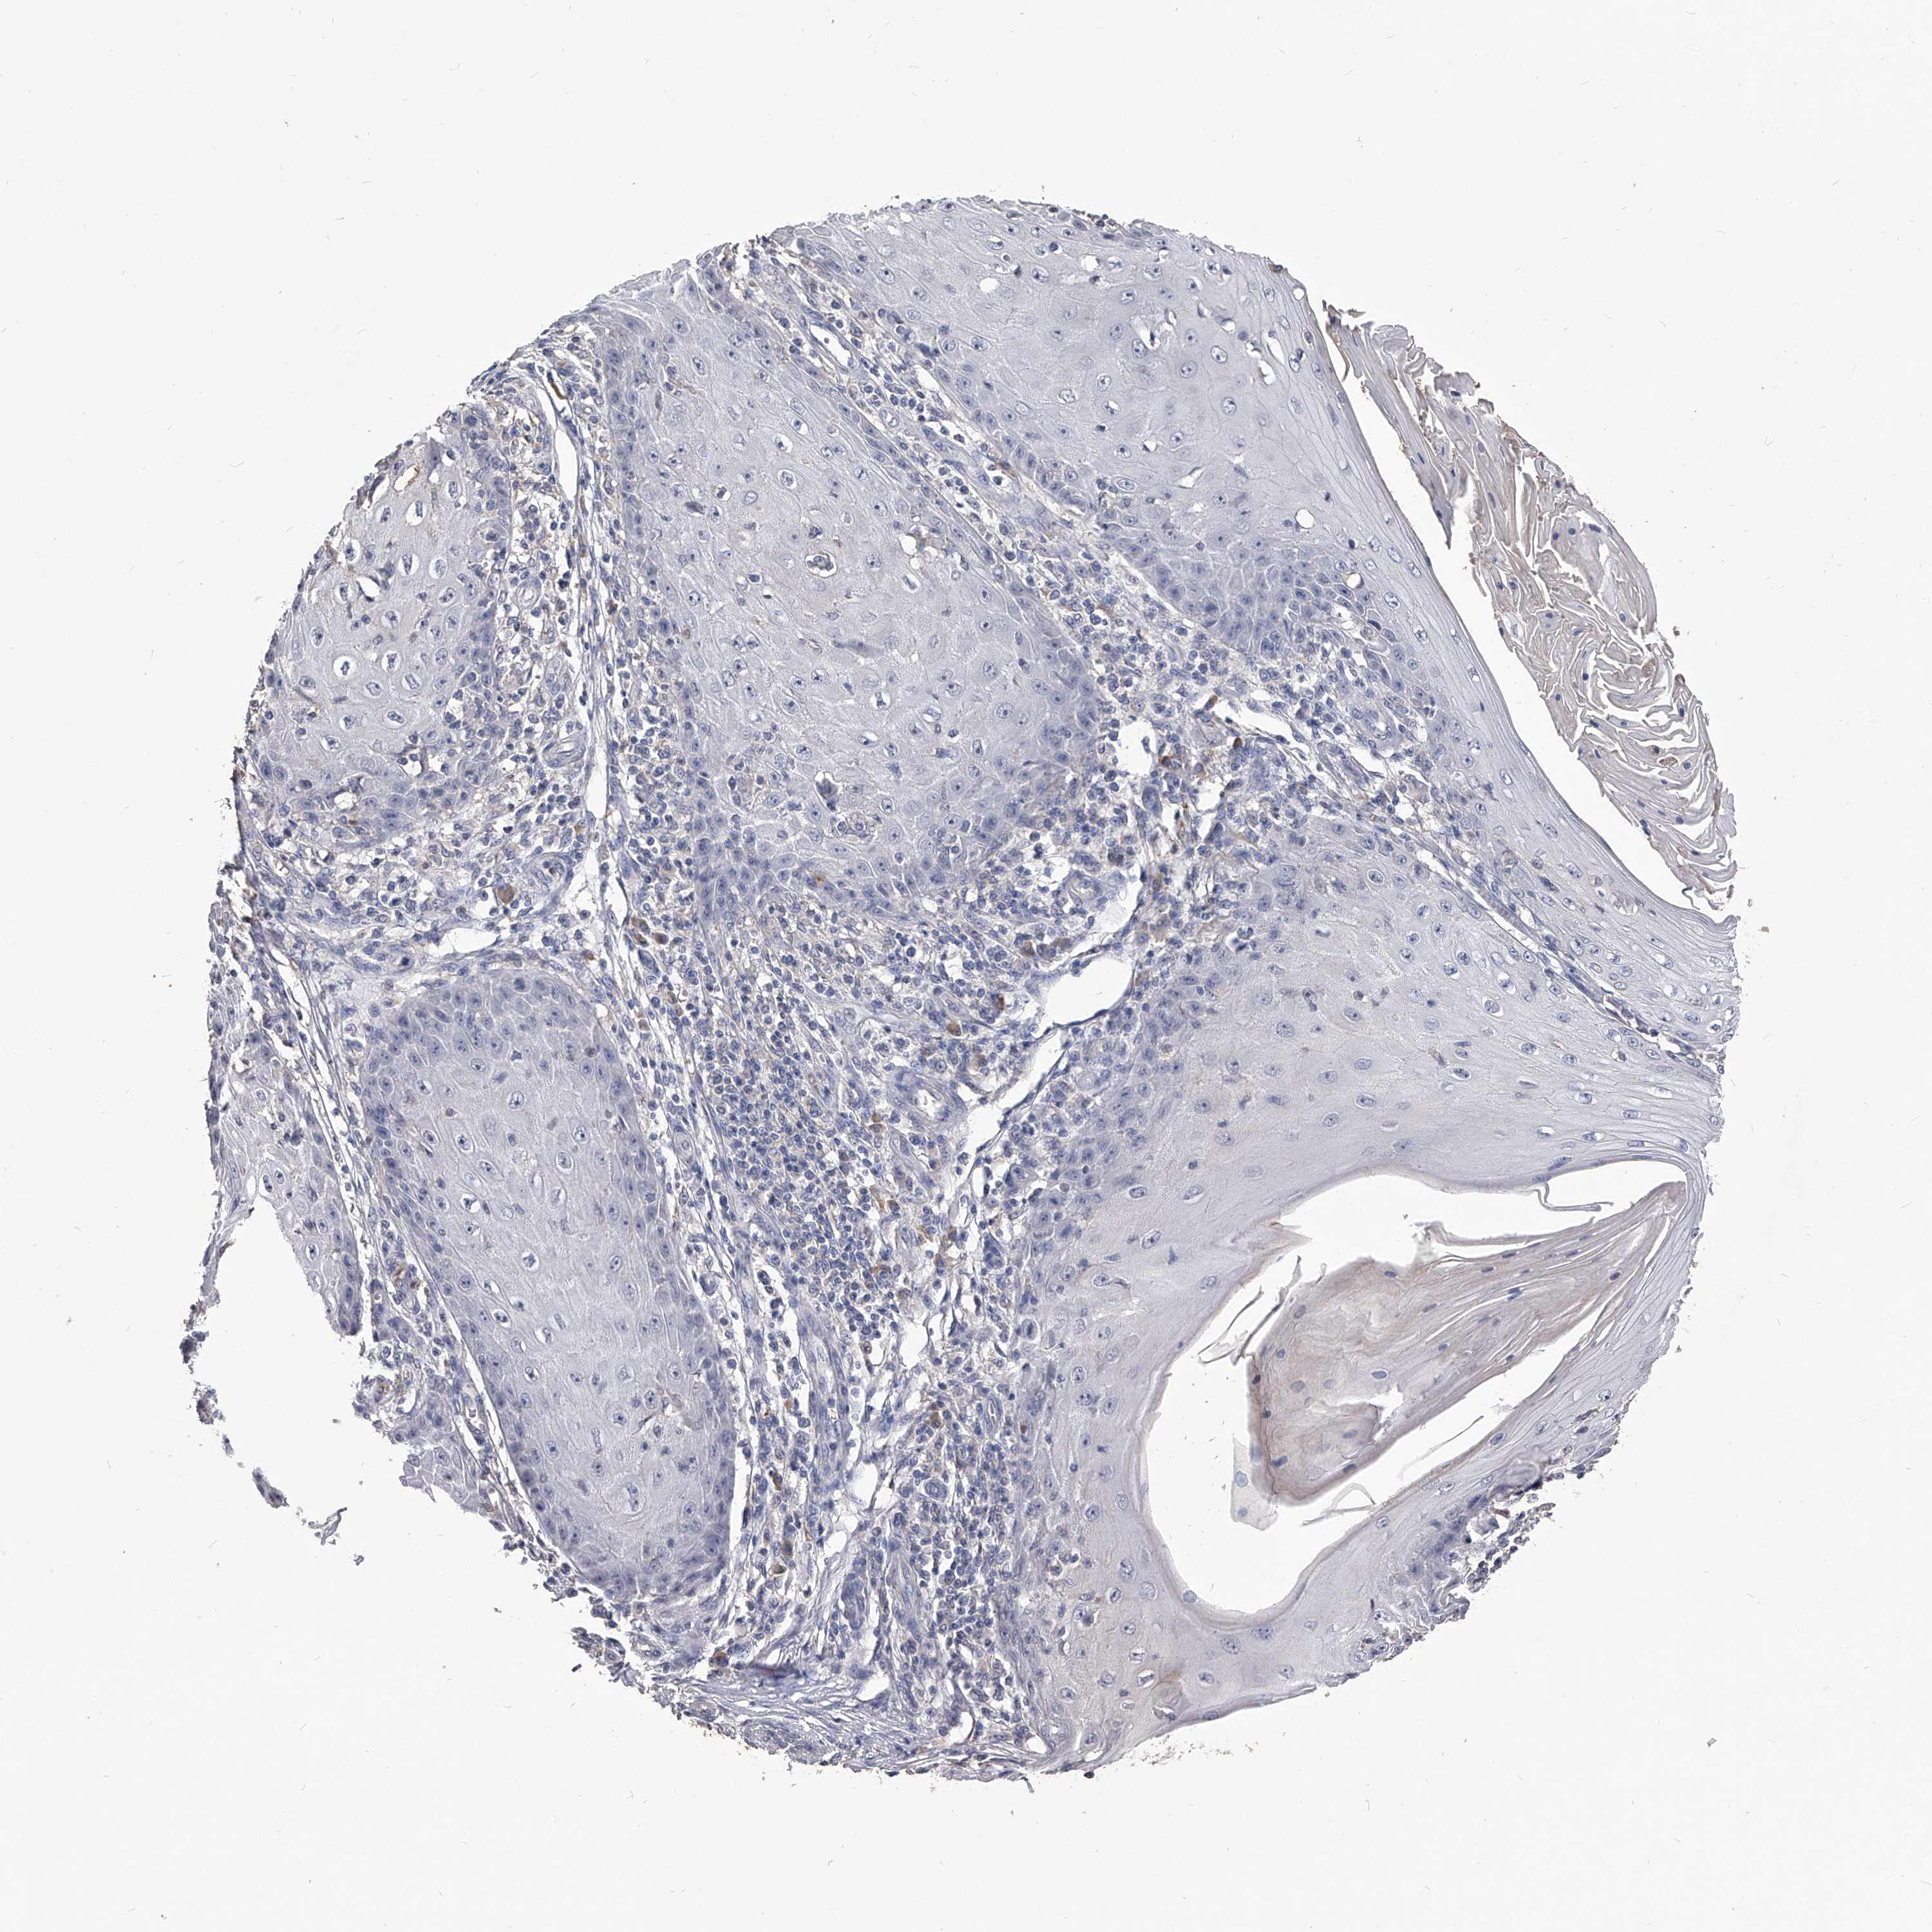

SKIN CANCER - Protein expressioni

A mouse-over function shows sample information and annotation data. Click on an image to view it in a full screen mode. Samples can be filtered based on level of antibody staining by selecting one or several of the following categories: high, medium, low and not detected. The assay and annotation is described here.

Each image is clickable and will lead to virtual microscopy that enables deeper exploration of all samples and also displays staining intensity scores, fraction scores and subcellular localization as well as patient and tissue information for each sample.

Antibody HPA029666

Antibody HPA029667

Antibody HPA029668

Antibody HPA029669

Staining

High

Medium

Low

Not detected

Basal cell carcinoma

Squamous cell carcinoma, NOS

Squamous cell carcinoma, metastatic, NOS